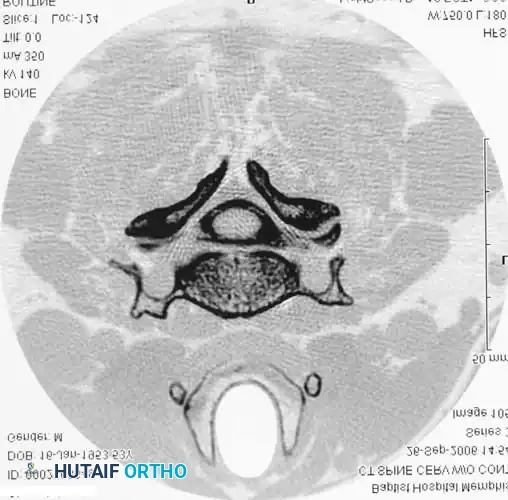

DIAGNOSTIC STUDIES Surgical Diagram

Axial CT of the cervical spine without contrast, demonstrating the osseous boundaries of the central canal and neuroforamina.

Multi-panel CT imaging demonstrating various reformatted views, essential for comprehensive 3D spatial understanding of spinal pathology prior to surgical intervention.